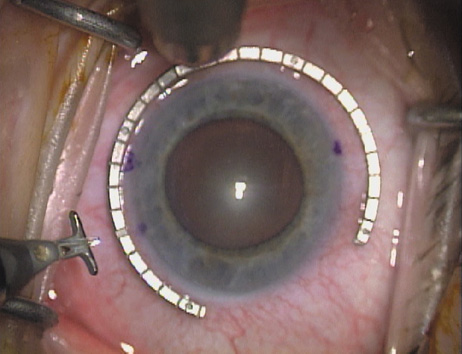

Case 1 is a 68-year-old male who presented for right cataract surgery. His refraction was −1.00 +2.25 × 80 and was recorded as reliable, consistent with his modest cataract density. Keratometry readings were 44.75 × 75 and 43.00 × 165. Corneal topography confirmed slightly more than 2.00 D of regular and slightly oblique cylinder. Consulting the nomogram, a plan was devised for a pair of LRIs to be centered over the 75-degree axis, with each incision delineating 45 degrees of arc. A single plane phaco incision was used and maintained at a size of less than 3.2 mm (Figs. 811).

Fig. 8. Steep meridian is confirmed intraoperatively by keratoscopy. In this left eye viewed from the temporal side, the “short axis” of the corneal mire is seen to be at the 75-degree meridian. (Reprinted from Hardten DR, Lindstrom RL, Davis EA. Phakic Intraocular Lenses: Principles and Practice. Thorofare, NJ: SLACK Incorporated, 2004, with permission.)

Fig. 9. The broad hash marks of the fixation ring/gauge are centered over the 75-degree meridian, using the 6:00 limbal mark for orientation. Alternatively, a Mendez gauge may be used. (Reprinted from Hardten DR, Lindstrom RL, Davis EA. Phakic Intraocular Lenses: Principles and Practice. Thorofare, NJ: SLACK Incorporated, 2004, with permission.)

Fig. 10. The single footplate diamond blade is inserted perpendicular to the corneal surface and at the peripheral most extent of clear corneal tissue. In this case, the nomogram calls for arcuate incisions of 45 degrees. Therefore, the incision is begun approximately 22.5 degrees to one side of the broad hash mark. (Reprinted from Hardten DR, Lindstrom RL, Davis EA. Phakic Intraocular Lenses: Principles and Practice. Thorofare, NJ: SLACK Incorporated, 2004, with permission.)

Fig. 11. Opposite relaxing incision is completed. (Reprinted from Hardten DR, Lindstrom RL, Davis EA. Phakic Intraocular Lenses: Principles and Practice. Thorofare, NJ: SLACK Incorporated, 2004, with permission.)